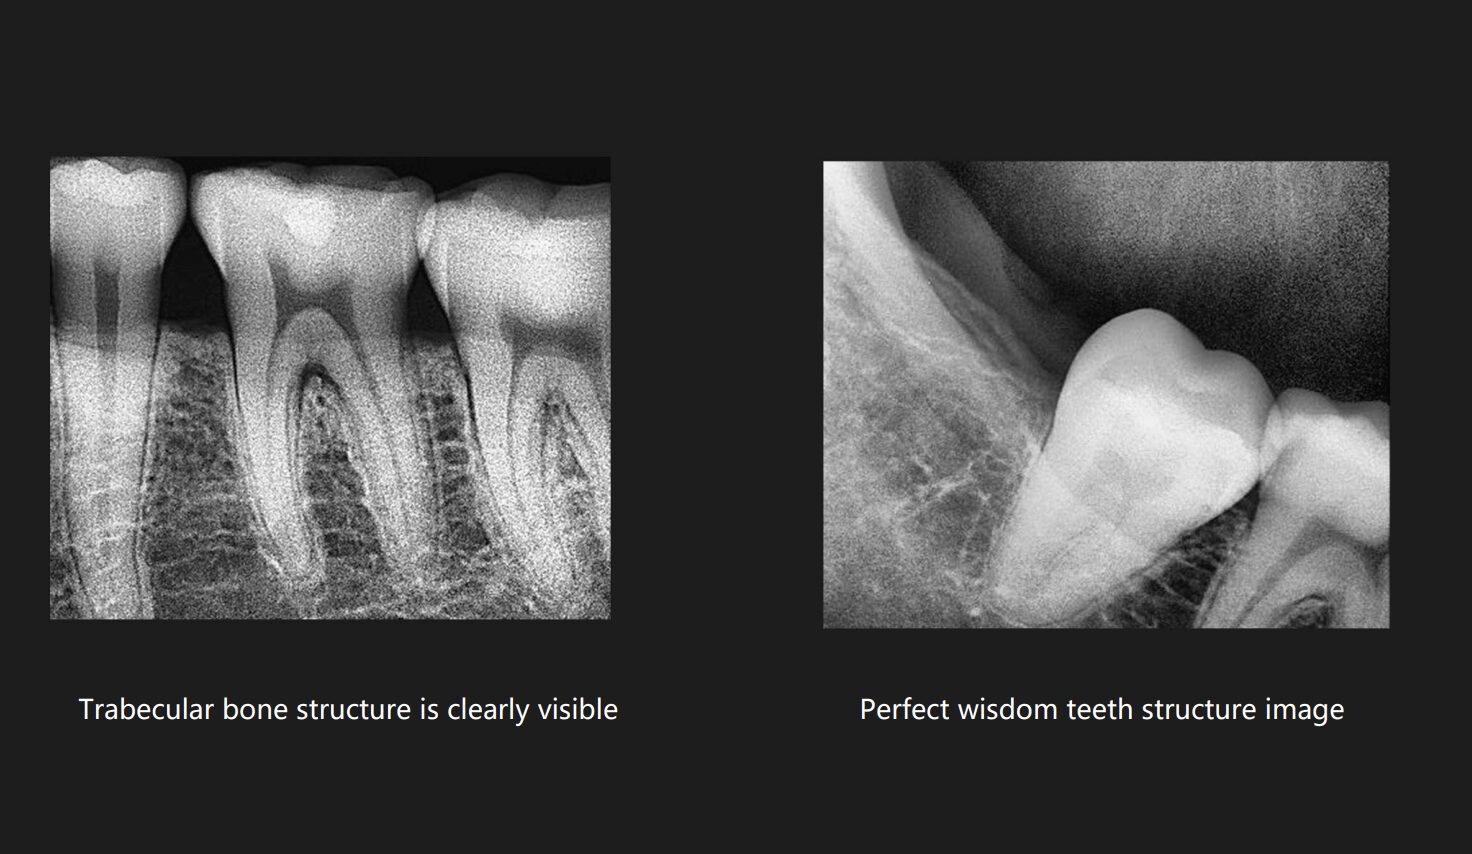

One of the first things to consider is the resolution. Higher resolution sensors provide clearer, more detailed images, which can make a significant difference in diagnosing conditions accurately. However, higher resolution often comes at a higher price. That’s where finding a balance between cost and performance becomes crucial.

In essence, an X-ray sensor captures the X-rays that pass through the patient’s body and converts them into digital signals. These signals are then processed to produce a detailed image of the internal structures. The core component inside the sensor is a material sensitive to X-rays, usually made of silicon or other high-grade semiconductors.